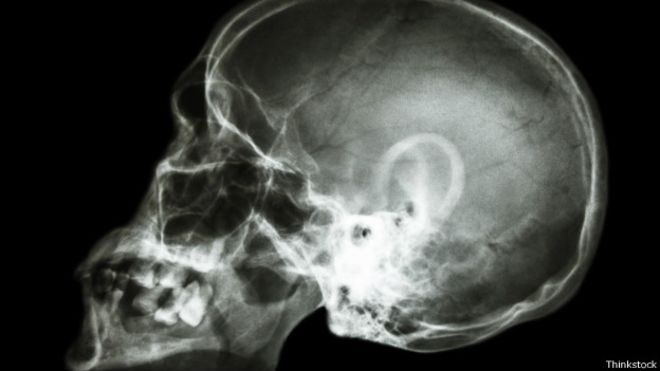

Con el objetivo de dar a conocer las consecuencias que dejan enfermedades o accidentes que ocasionan lesiones cerebrales, un blog compila las experiencias personales de quienes han pasado por estas situaciones.

La organización benéfica Headway East London, en Reino Unido, ofrece apoyo a pacientes que han sufrido una lesión cerebral adquirida (ABI, por sus siglas en inglés) y, para ayudarlos a superar lo ocurrido, compila sus historias: cómo eran sus vidas antes y cómo cambiaron tras la enfermedad.

Cuando llegó al departamento de emergencias del hospital, le diagnosticaron un quiste en el cerebro, que requirió una operación en la que se removió una parte del cráneo.

Estuve en coma por un par de meses.Tenía una especie de tornillo que salía de mi cabeza porque me quitaron una parte del cráneo para aliviar la presión.